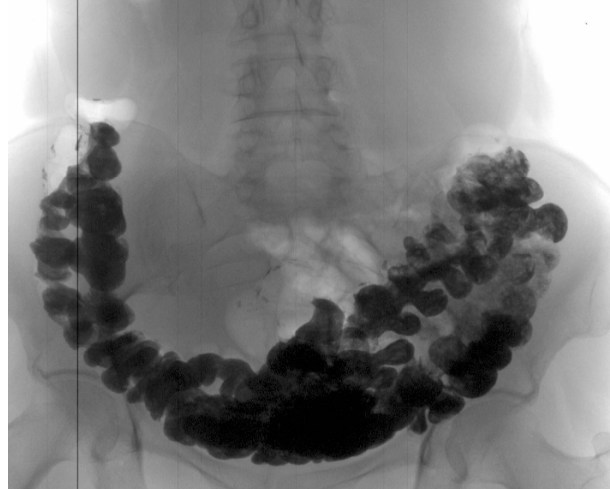

‘’Рак товстої кишки у жінки зі скаргою на часті закрепи’’

‘’Рентгенографія калового каміння в товстій кишці’’